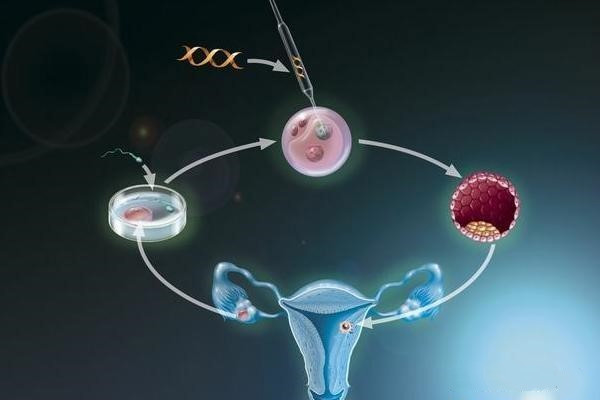

成功怀孕会经历以下几不同的阶段。- 精子必须到达并穿透并使女人的卵子受精。 - 产生的受精卵必须分裂并形成胚泡。 - 胚泡到达子宫并植入子宫内膜。 - 植入的胚泡...

试管婴儿精子和卵子结合形成受精卵,发育成胚胎,发育的胚胎需要在子宫内定居,胚胎着床需要多长时间?在卵子受精后,从输卵管到子宫需要几天的时间,胚胎继续生长和分裂,最...

受精过程中,二代试管婴儿技术-卵胞浆内单精子注射(ICSI)的方法用的比较多;取精方法则是通过手淫方式或外科取精过程来取得精子,然后将其进行冷冻保存,这使得我们可...

由于单个基因的问题而引起的家族遗传病,如果家庭成员其中一个儿童已经出现了类似疾病,早期诊断该疾病非常重要,生活中,很多这种单基因遗传病诊断只能在怀孕期间发现,但是...

胚胎植入前基因诊断(PGD)正越来越多地用于试管婴儿,并显著提高试管婴儿成功怀孕的几率,尤其是此前那些原因不明的试管婴儿失败。据统计,一半以上的试管婴儿失败其实并...